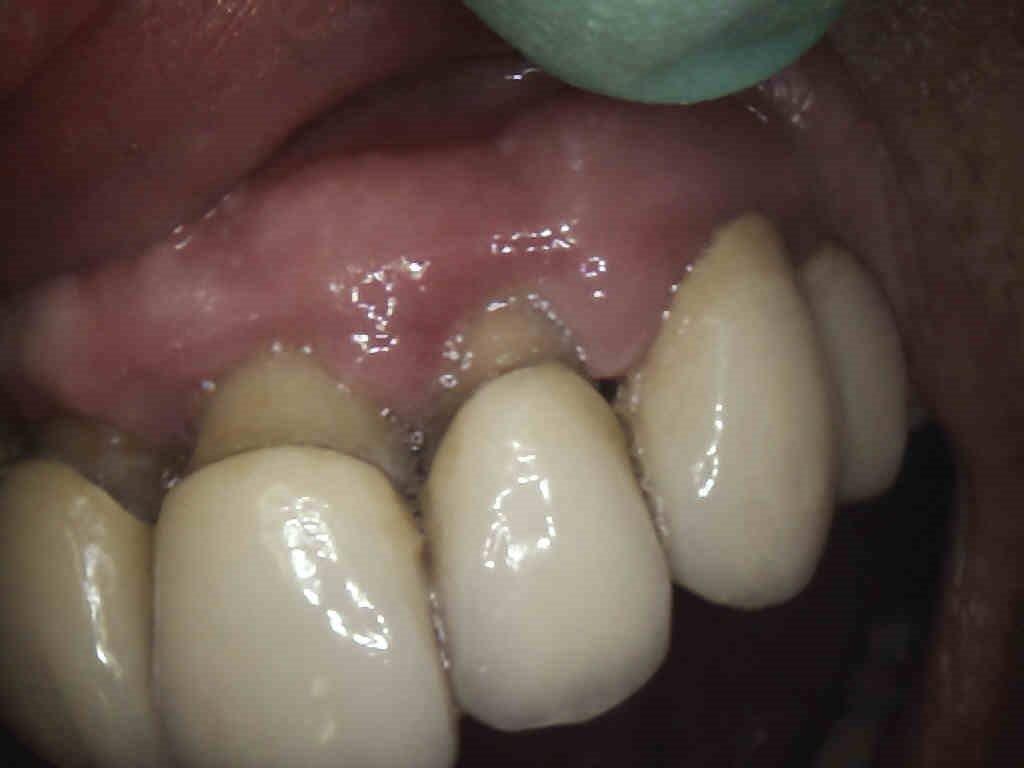

2 – Aspetto precure dell’arcata superiore destra